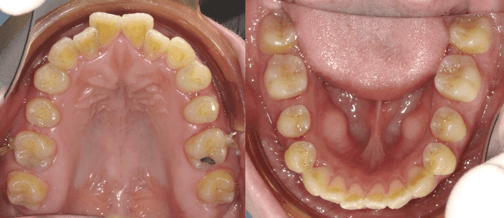

24岁拔磨牙大牙智齿前移替代7号牙牙齿矫正记录 知乎

戴牙套讓我變得更有自信 分享 文長牙齒圖多哦